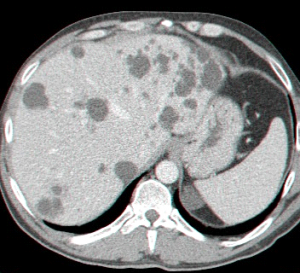

- בטומוגרפיה ממוחשבת ניתן לראות גוש בכבד (תצלום 25.10).

| תצלום 25.10: ציסטות מרובות בכבד. מימין הציסטות הן חלק ממחלה פוליציסטית מערכתית. משמאל ציסטות המוגבלות לכבד בלבד. | |

|---|---|